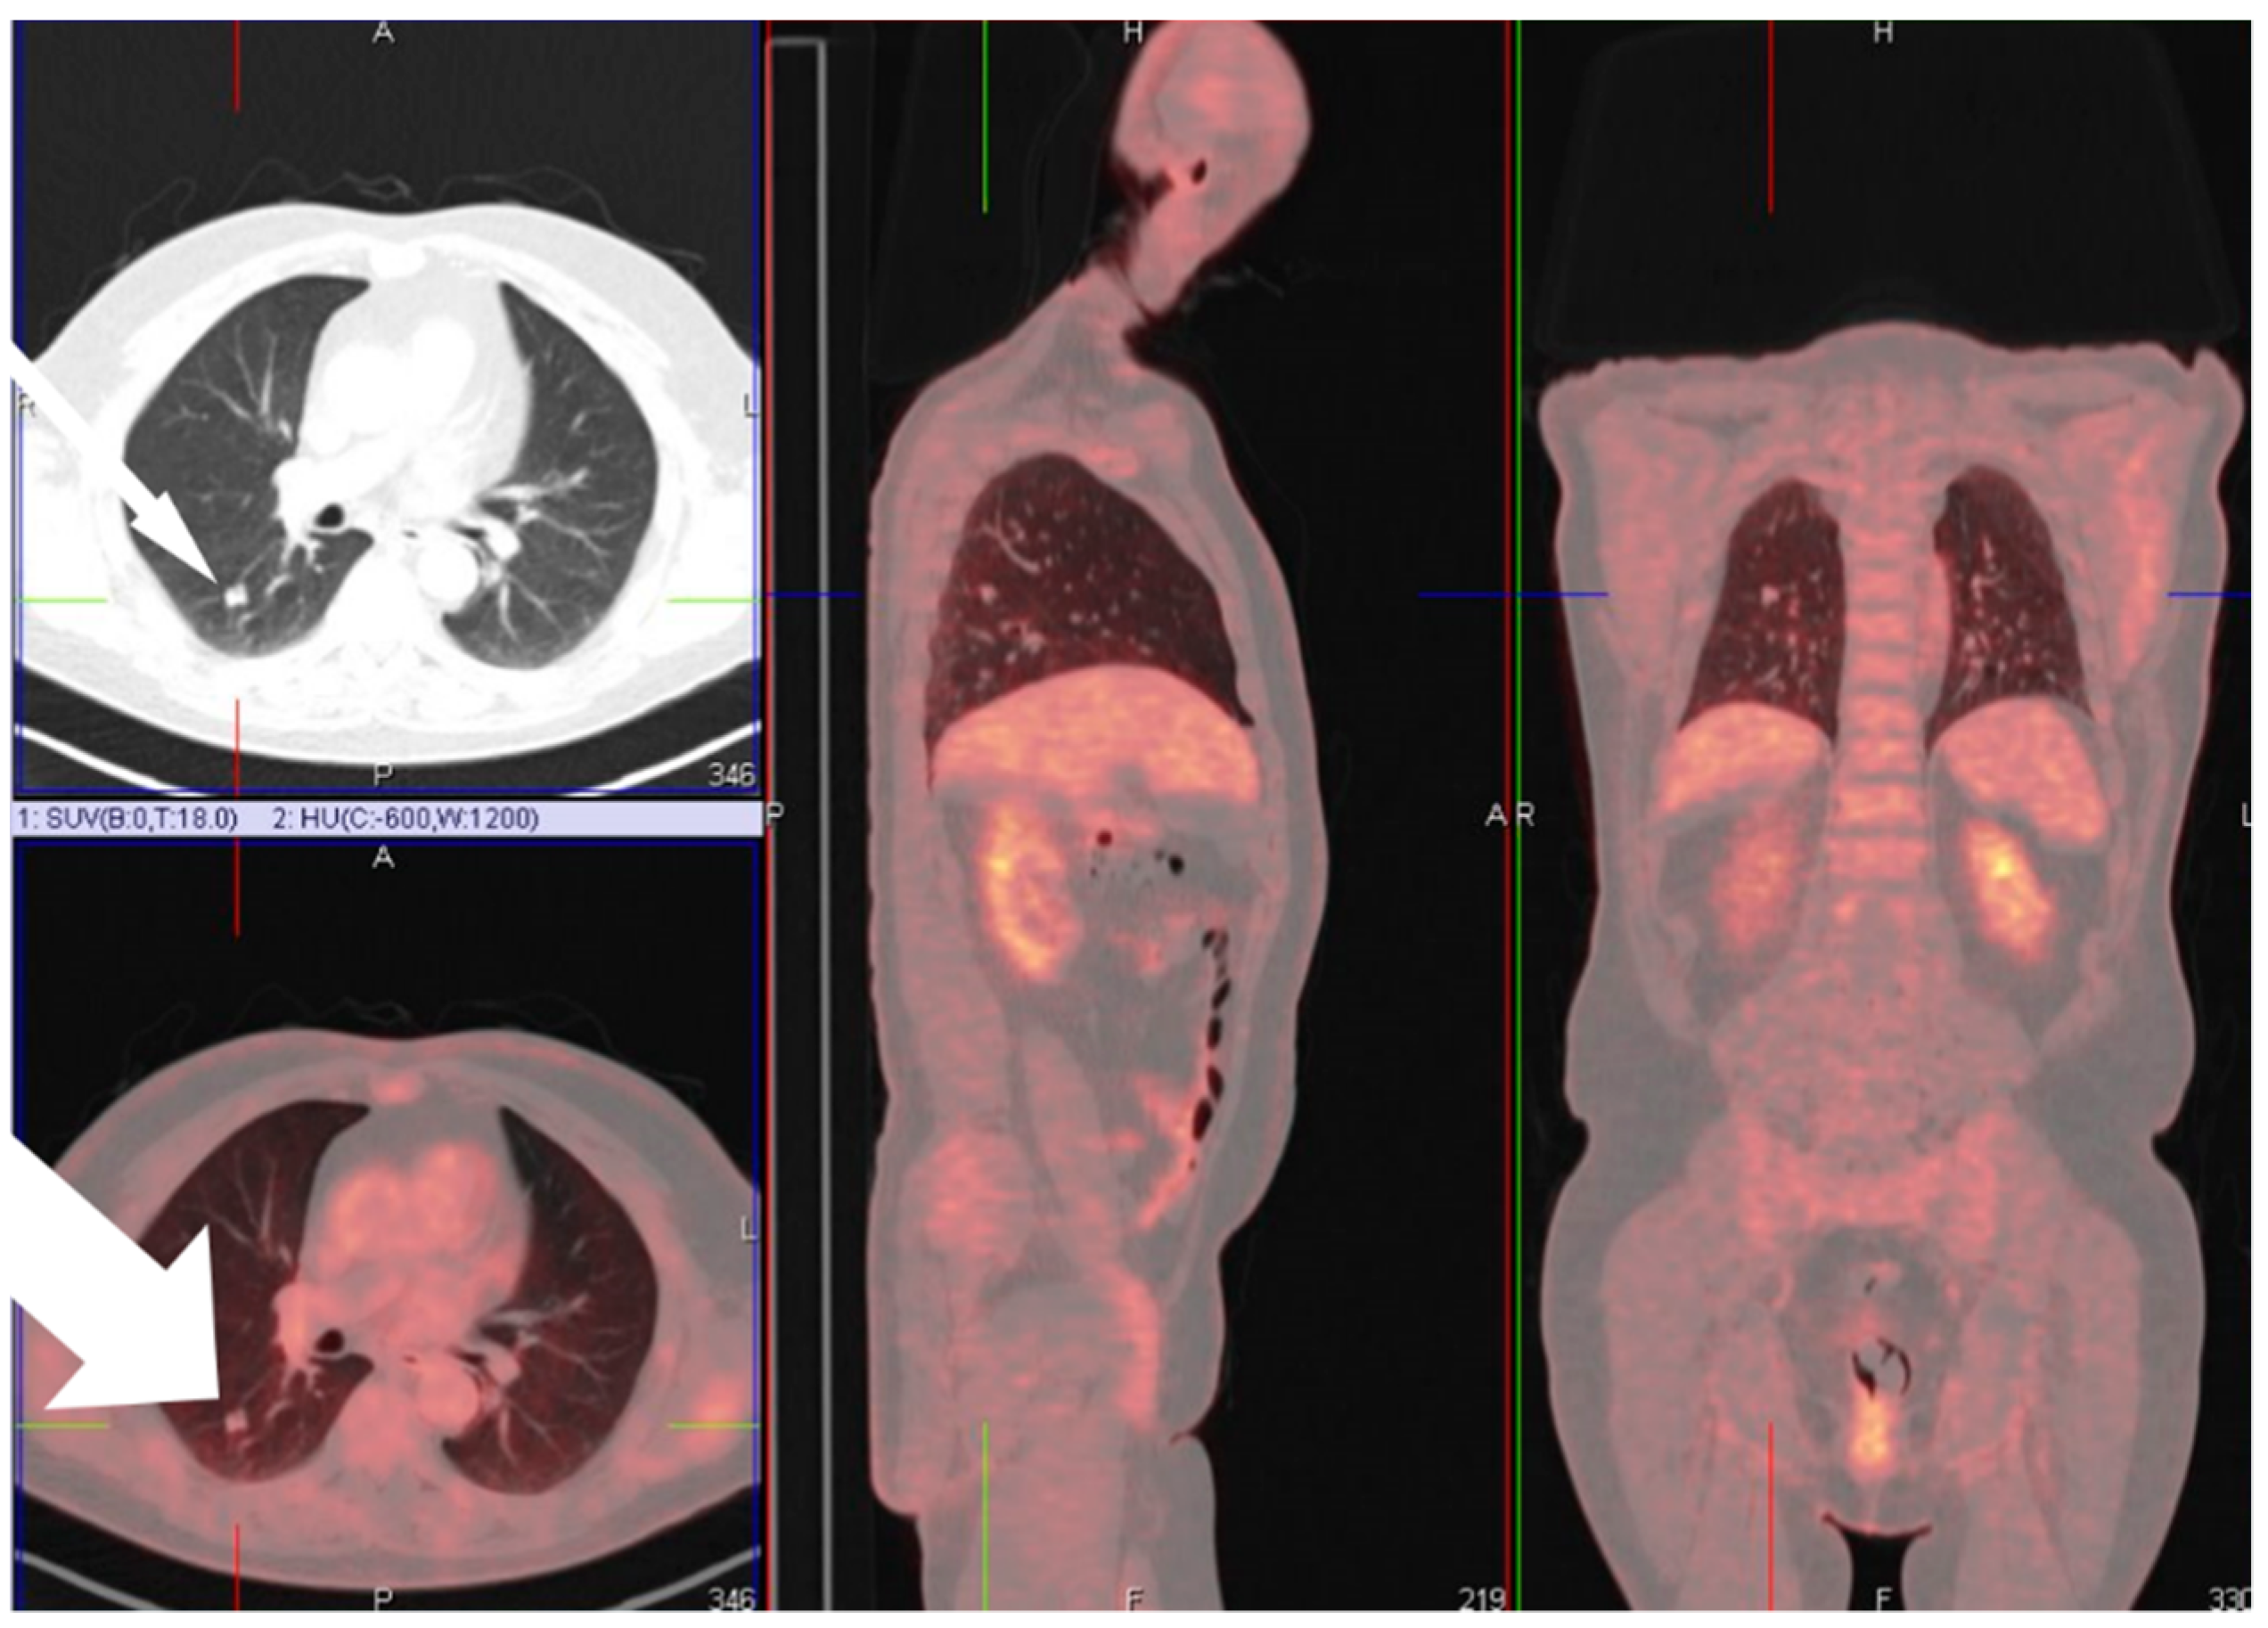

Most patients were male (28 patients, 82.4%) with a mean age of 63 years upon diagnosis (range 41 to 82). Nine patients (26.5%) had a history of obstructive lung diseases such as asthma or chronic obstructive pulmonary disease (COPD), and only three patients (8.8%) suffered from interstitial lung fibrotic disease. Two patients (5.88%) were diagnosed with congestive heart failure. Suspected malignancy was, in all cases, the reason to perform surgery. This oncologic diagnosis was confirmed in 19 patients (55.9% of cases). We could not demonstrate any correlation between the imaging and operative findings. Due to their small size, not all pathologically proven ossifications could be visualized on chest CT scans. A representative image is presented in Figure 2, where a positron emission tomography combined with computed tomography (PET-CT) scan showed a moderate FDG uptake with clear evidence of calcification or ossification in the lesion on the CT alone.

Figure 2. PET-CT showing moderate FDG-avidity of a lesion on PET scan in the right lower lobe with evidence of calcification or ossification on the diagnostic CT. FDG, fluorodeoxyglucose.

We observed a clear predilection for the lower lobes (left lower lobe in 12 cases, or 35.3%, and right lower lobe in eight cases, or 23.5%), and most ossifications were found in the right lung (21 cases, 61.7%) (Figure 2). We identified 24 cases of nodular ossification (70.6%). In six patients (17.6%), bone marrow formation was observed, equally divided between the nodular and dendriform ossifications.